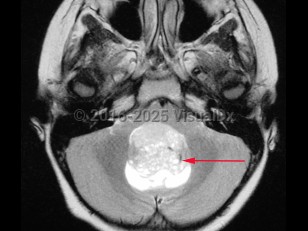

Imaging Studies image of Medulloblastoma - imageId=8343471. Click to open in gallery.  caption: '<span>Axial MRI demonstrating hyperintense medulloblastoma in the posterior fossa in a pediatric patient.</span>'

Axial MRI demonstrating hyperintense medulloblastoma in the posterior fossa in a pediatric patient.